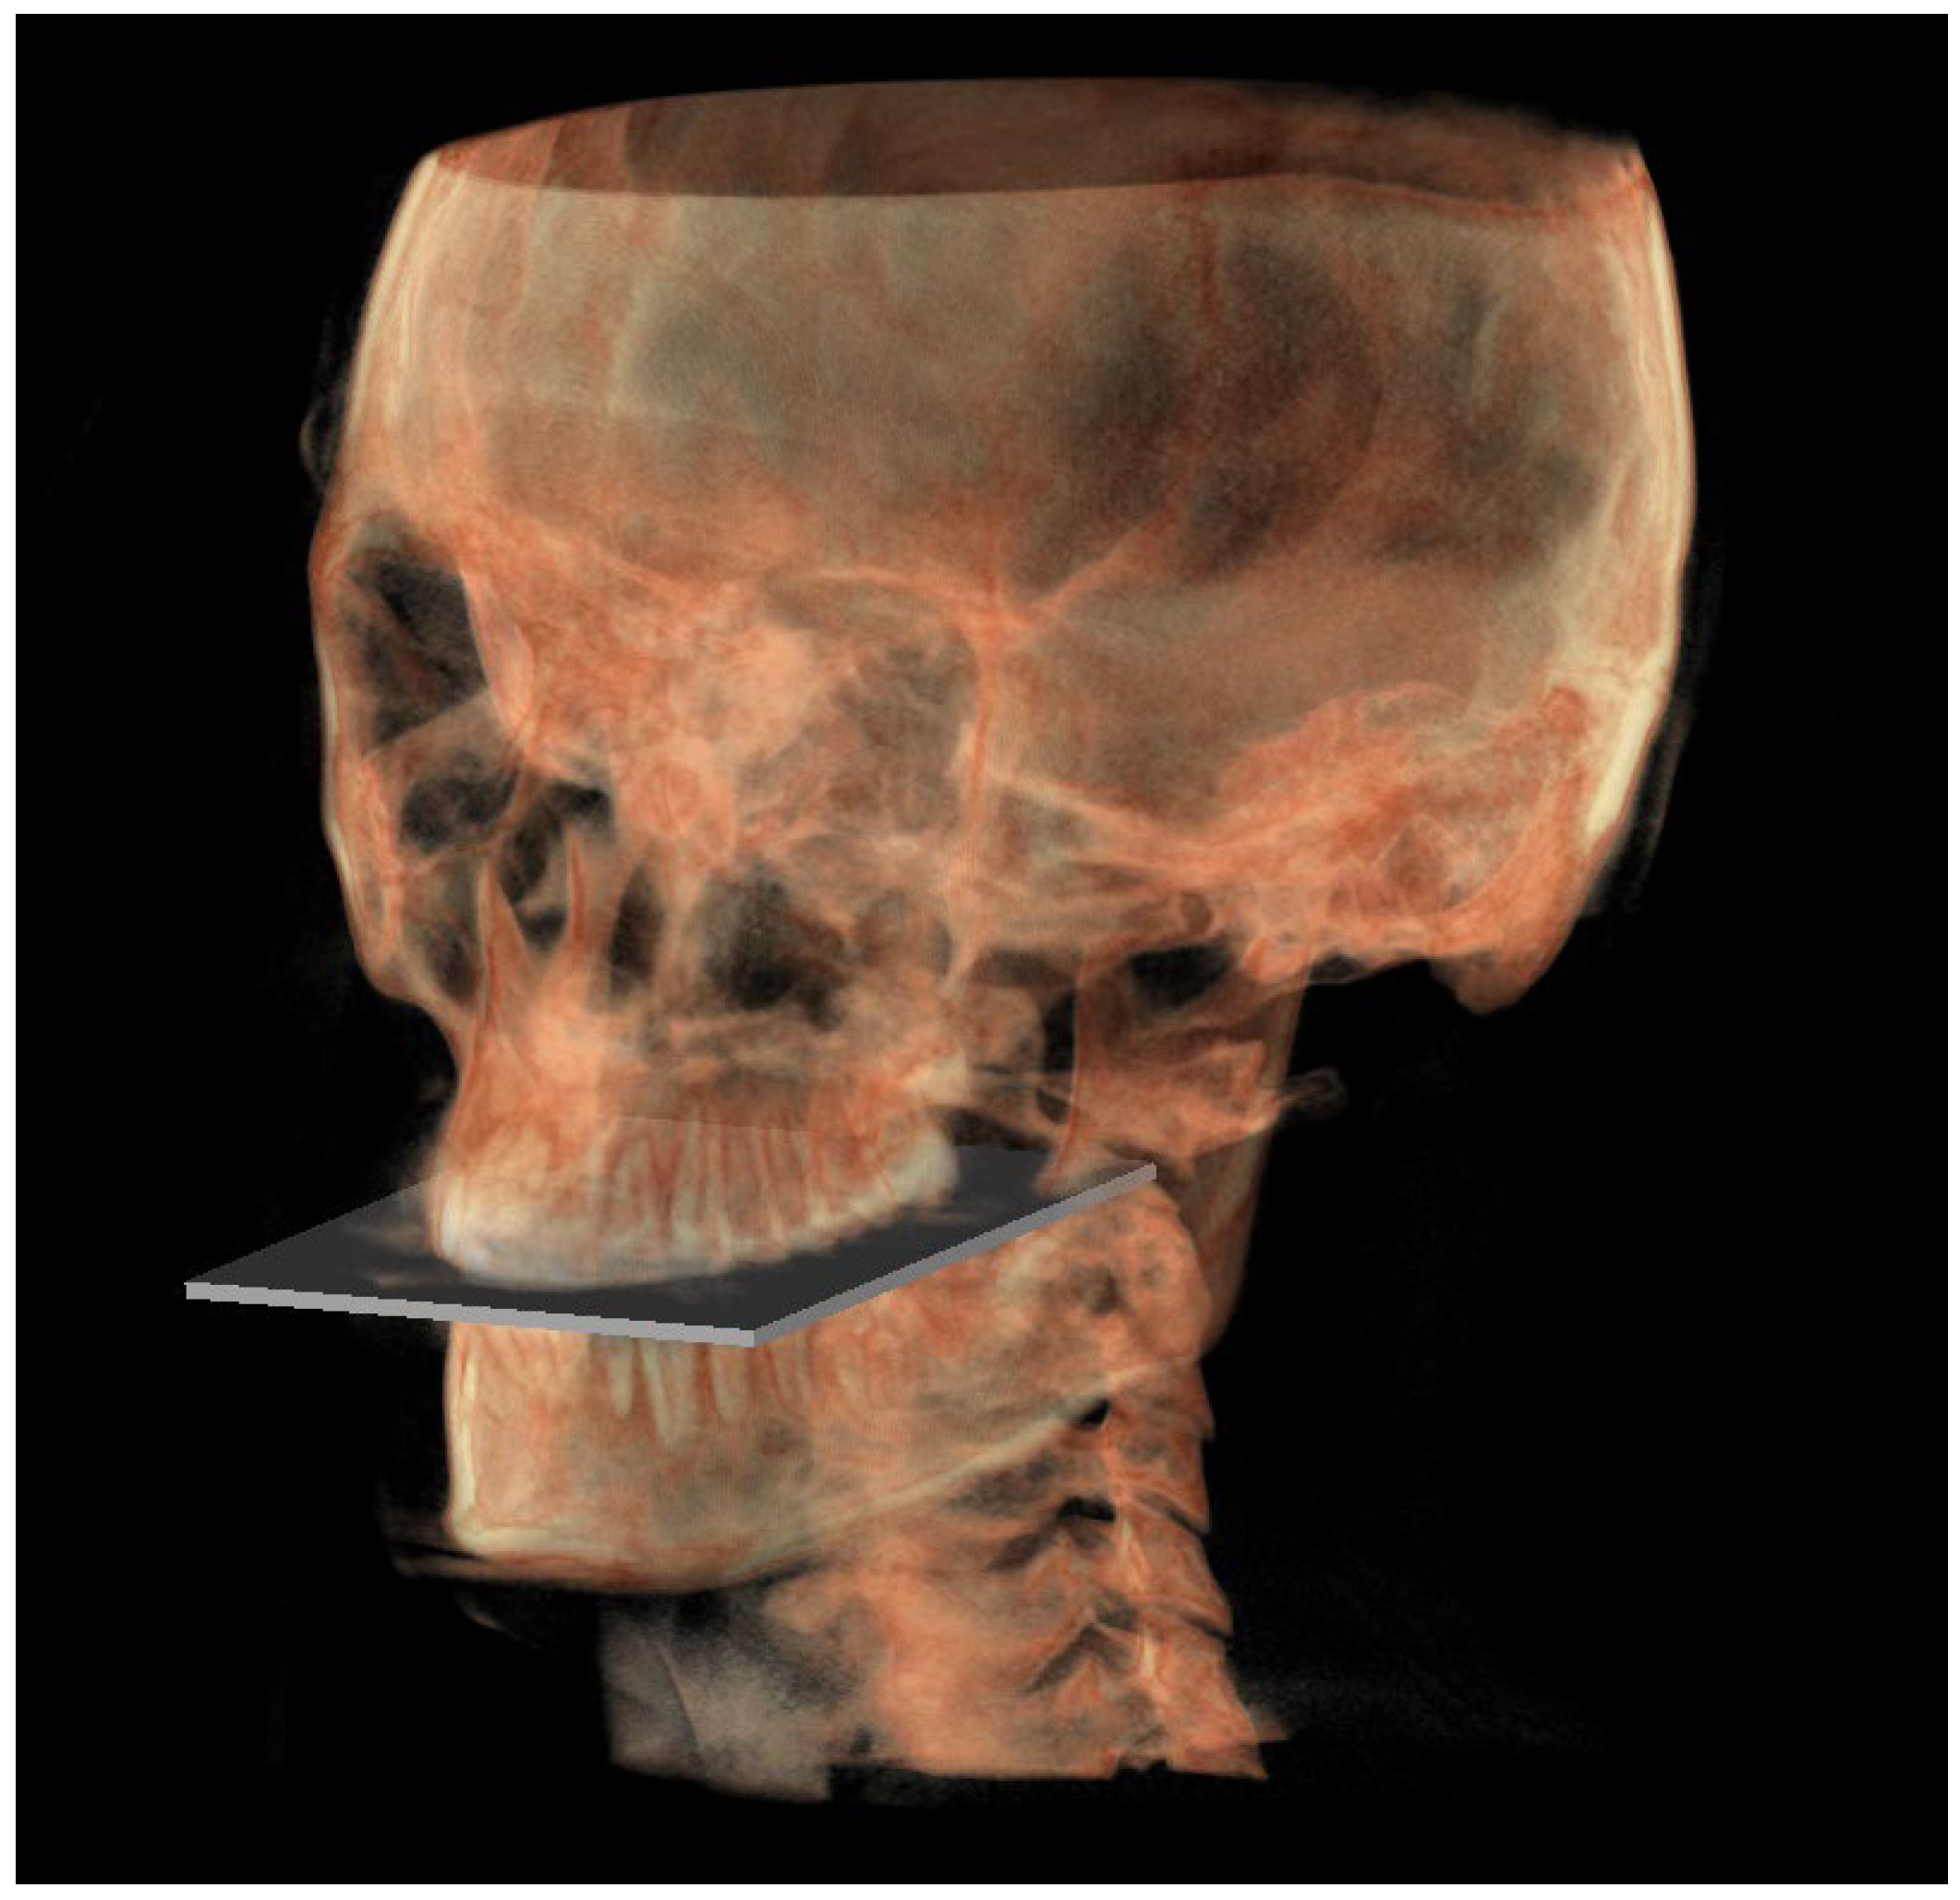

- The functional occlusal plane (FOP) (Figure 6) was identified by the posterior occlusal contact right side (rPoc), posterior occlusal contact left side (lPoc) and the middle point between the right and left anterior occlusal contact (mAoc). To adequately locate the mAoc, it is advisable to draw a line on the transversal view from the right mesial premolar contact to the left one to have a reference along which measure the distance.